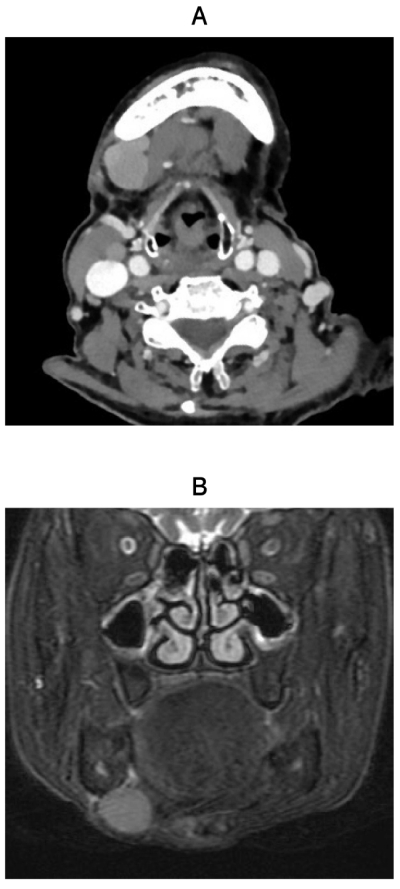

86歳の女性。顎下部の無痛性の腫脹を主訴として来院した。1か月前から自覚し、徐々に増大してきたという。初診時の造影CT、MRI脂肪抑制T2強調像及び生検時のH-E染色病理組織像を別に示す。

診断名はどれか。1つ選べ。

a. 血管腫

b. 脂肪腫

c. 神経鞘腫

d. 多形腺腫

e. 悪性リンパ腫